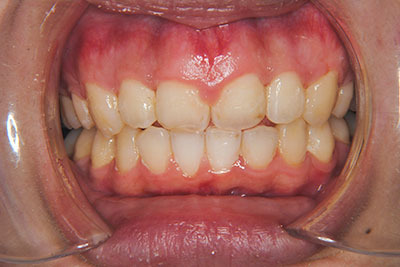

おとなの方でも矯正治療をあきらめないでください!

矯正歯科治療は子供の頃だけしかできない……

子供の頃に比べ大人になったら治療期間がすごく長い……

というようなイメージをお持ちではありませんか?

子供の頃に矯正治療を行う方が治療期間が短く済むというのは、確かですが、矯正治療は患者様の意識も重要です。

いくら歯が動き易くとも、本人がやる気でなければ効果は出ませんし、むし歯発生のリスクも高まります。おとなの方は顎の成長が終わっているため、治療の計画が立てやすいとも言えます。「もう大人だから…」とあきらめず、一度ご相談ください。